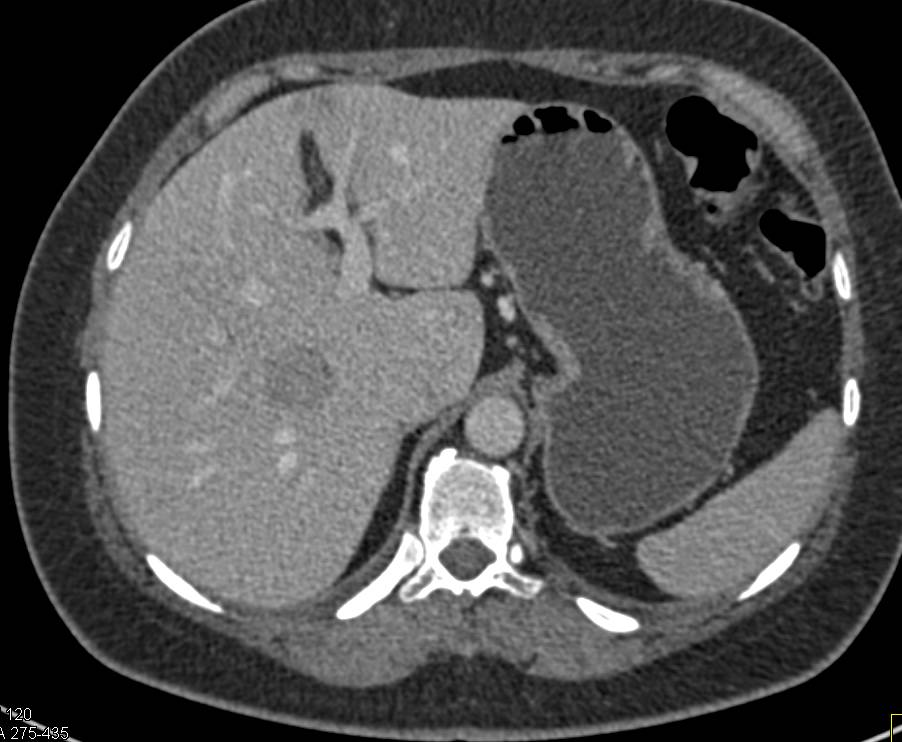

Хирургические процессы при эмболизации гемангиомы на фото

Раздел: Снимки-откровения